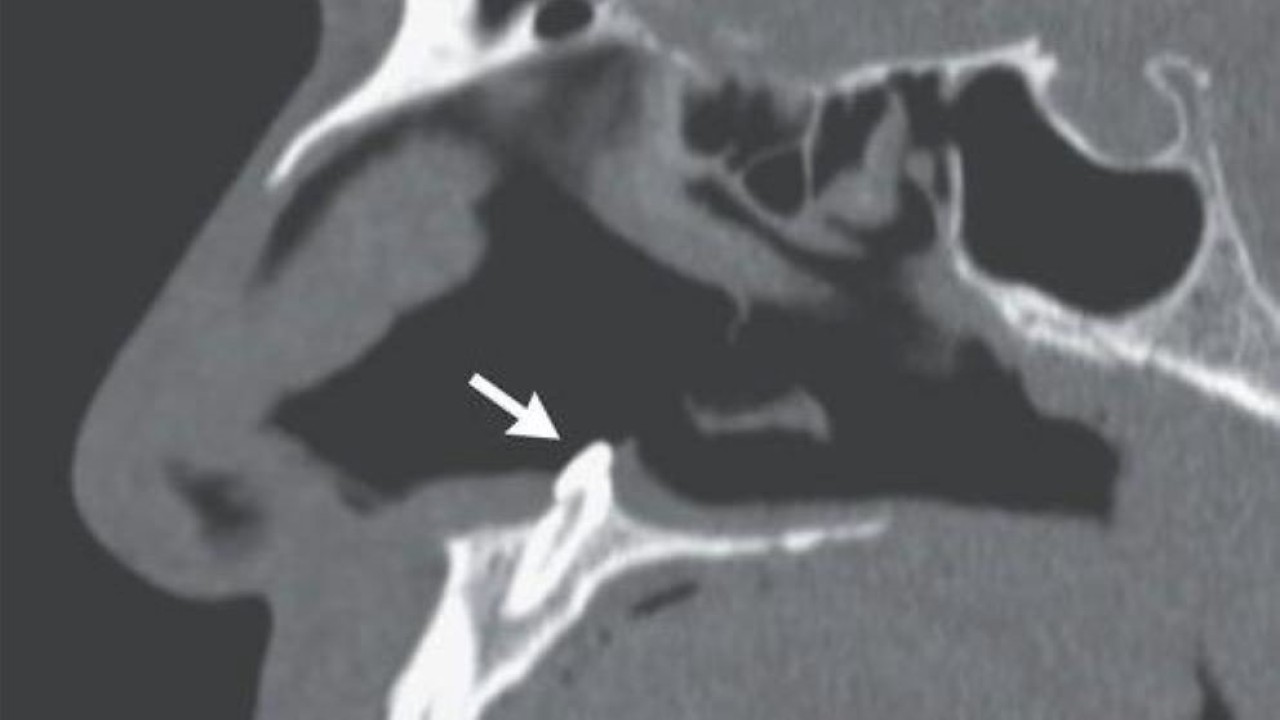

Ternyata, kata dokter, pria itu memiliki gigi yang tumbuh di rongga hidungnya, seperti dikutip dari UPI, Jumat (25/2/2022). Drs. Sagar Khanna dan Michael Turner, ahli bedah di Mount Sinai Health System di New York, mengatakan dalam sebuah studi kasus yang diterbitkan di New England Journal of Medicine.

Disebutkan jika pria berusia 38 tahun itu memberi tahu dokter bila dia mengalami kesulitan bernapas melalui lubang hidung kanannya selama beberapa tahun. Dokter menemukan dia memiliki septum yang menyimpang, yakni suatu kondisi di mana partisi antara saluran hidung didorong ke satu sisi, dan rinoskopi yang dilakukan dengan kamera kecil menemukan penyebabnya, gigi yang tumbuh di 'dasar lubang hidung kanan'.

Gigi ektopik, istilah untuk gigi yang tumbuh di tempat abnormal, berukuran panjang sekitar 0,6 inci. Ahli bedah mengatakan mereka mencabut gigi tanpa komplikasi, dan pria tersebut melaporkan selama kunjungan tindak lanjut tiga bulan setelah prosedur di mana dia sudah dapat bernapas dengan normal melalui kedua lubang hidungnya.